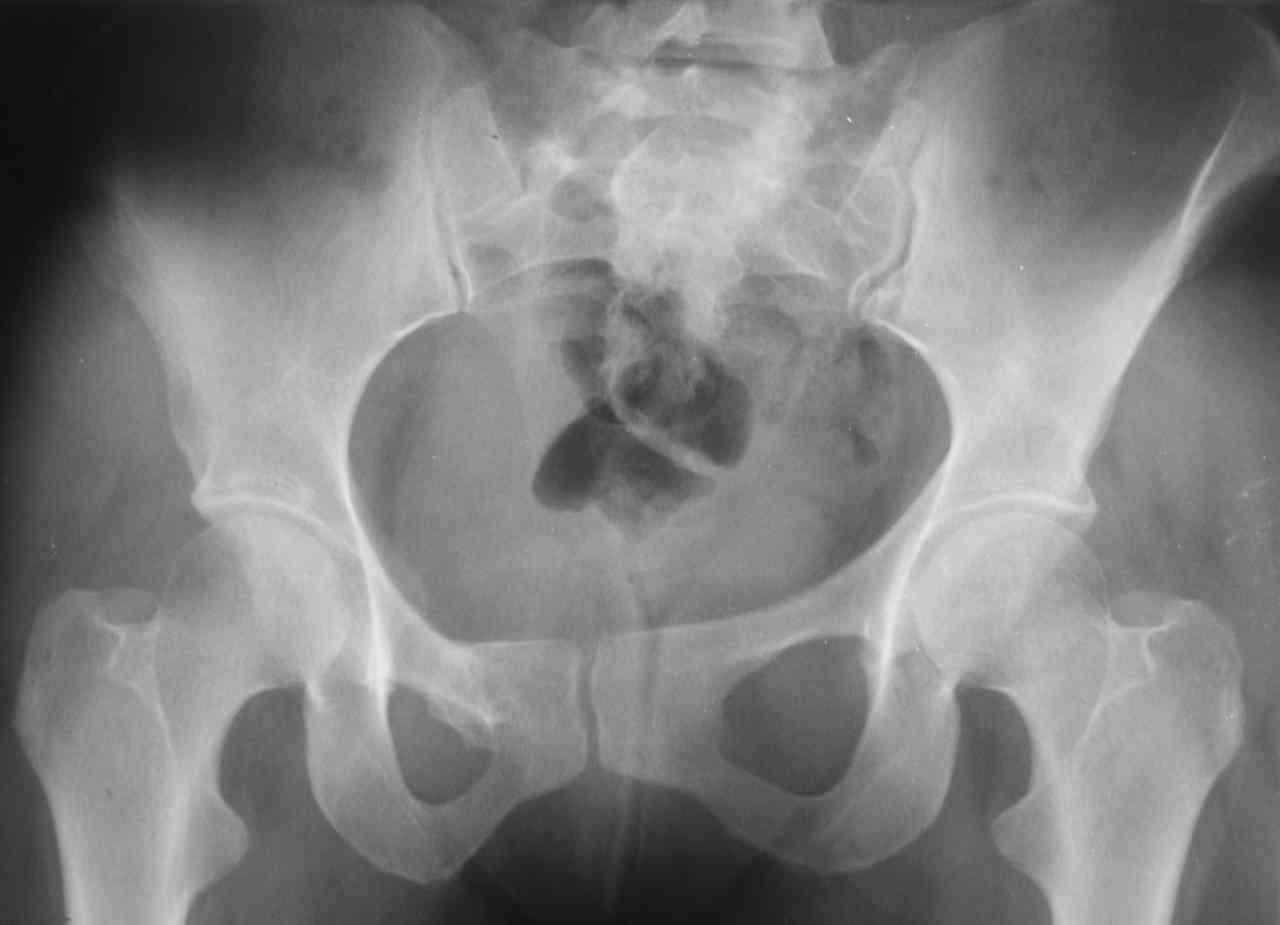

13/03/03 |  13/03/03 |  13/03/03 |  15/09/06 |  15/09/06 |  07/03/07 |  07/03/07 |  19/12/06 | К нам в клинику поступила пациентка 30 лет с диагнозом: Постравматическая ротационная стабильная деформация тазового кольца. Относительное укорочение левой н\конечности на 1 см. Левосторонний компенсаторный сколиоз 2 ст. Болевой синдром. травма автодорожная в январе 2003г. Пассажирка переднего сидения ваз 2109. лечились положением по Волковичу. С марта 2003 года жалуется на боли в тазу, ппояснице усиливающиеся при движении.В настоящее время жалобы на боли в области крестца, КПС больше слева, в пояснично-крестцовом отделе позвоночника. неприятные ощущения, щелчок при выпрямлении правого тазобедренного сустава из положения полного сгибания. боли в тазу появляются при ходьбе ч\з 100 м, так же при вставании из положения сидя, после сидения в течении 2-3 часов. при ходьбе более 100 м появпяется зябкость стоп больше справа. ходит при помощи трости в правой или в левой руке. без трости боли появляются сразу после начала ходьбы. пальпация болезненна в паравертебральных точках средне-грудного и пояснично-крестцового отделов позвоночника, КПС с обеих сторон. Объем движений в тазобедренных суставах полный.правый КПС заблокирован. симптомы натяжения с обеих сторон отрицательны.С 2003г. лечится консервативно, получала ЛФК, массаж, физиолечение - без эффекта. в 2005г. лечилась в санатории с ортопедическим уклоном, получала плавание в минеральной воде, магнитотерапия, массаж, ЛФК. отмечала умеренное улучшение в течении 2 недель.Вопросы:надо ли оперировать, т.е. устранять относительное укорочение левой н\конечности и как?Если не оперировать, то как лечить консервативно?Р-граммы, КТ прилогаются.

Проблема Вашей пациентки находится на границе интересов специальностей ортопедия (вертебралогия) и неврология (нейрохирургия), вероятно, поэтому так мало откликов на ваше обращение. Представленные рентгенограммы не все информативны (особенно спондилограммы от сентября 2006 года). Вероятно, необходимы дополнительные методы исследования к.т. МТГ, ЯМРТ, миелография.

Уважаемый Алексей. Описанные Вами клинические проявления указывают на нестабильность левого крестцово-подвздошного сочленения. Такие больные встречаются не редко (за последние 6мес.в нашей клинике оперировано 3 больных со сроками давности от 6мес. до 1 года). К сожалению рентгенологически их трудно обьективизировать. На КТ это проявляется артрозом и костными разрастаниями КПС. В Вашем случае рентгенограммы и представленные томограммы ничего не дали. Можно попробовать посмотреть связочный аппарат КПС на МРТ хотя не уверен что Вы получите окончательный ответ. Если Вы будете убеждены в этом диагнозе то выход один костно-пластический артродез левого крестцово-подвздошного сочленения с фиксацией канюлированными шурупами. Заманчиво конечно и устранить ротационное смещение половины таза, но это на Ваше усмотрение.

почему она должна возникнуть? Сломан вроде крестец, хотелось бы посмотреть функциональные снимки таза.

Уважаемый Максим. Снимки от 7.03.07 и есть функциональные, т.е. стоя на правой, и левой ноге.